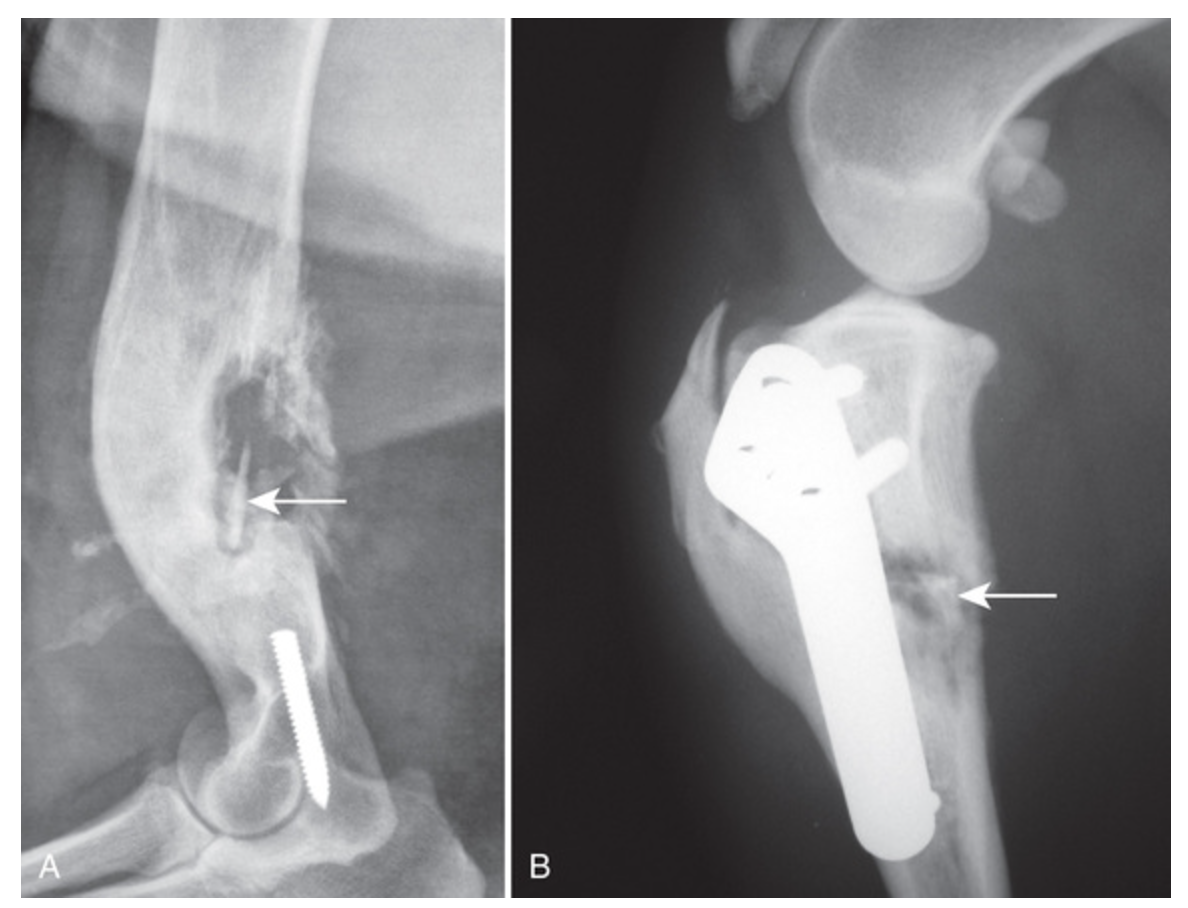

What is the imaging diagnosis in the following two images?

A

What are some radiographic changes associated with post-traumatic osteomyelitis?

Cortical resorption, periosteal proliferation, loss of trabecular markings +/- sequestrum and involucrum